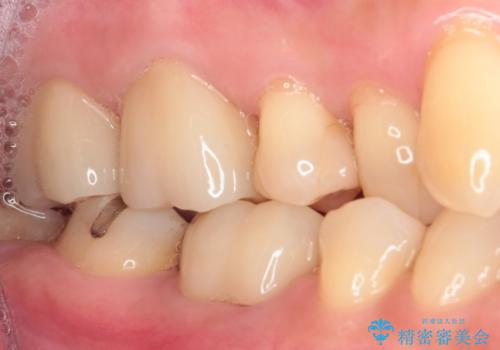

知覚過敏の症状はなくなり、希望通りの白い歯になったと、患者様は大変満足されました。